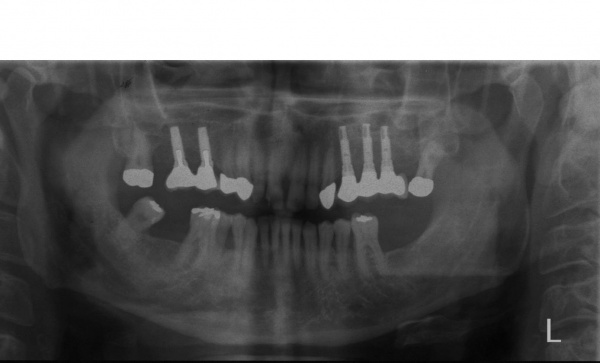

Der Erstbefund zeigte eine generalisiert entzündliche marginale Gingiva mit generalisierter Blutungsneigung bei Sondierung. Die approximalen Sondiertiefen waren durchgehend erhöht und betrugen im Molarenbereich bis zu 12 mm (s. Abb. 4). Es lagen multiple Zahnlockerungen vor, eine Zahnlockerung des Grades II zeigte sich an den Zähnen 11, 25, 26, 38, 37, 47; Grad III am Zahn 24. Harte Beläge in der Unterkieferfront, generalisiert weiche Beläge (API 62 %). Wurzelkaries an 24. Suffiziente Brückenversorgung im I. Quadranten. Die Panoramaschichtaufnahme von Juni 1998 (s. Abb. 4) zeigt einen generalisierten horizontalen Knochenabbau mit vertikalen Einbrüchen in regio 17, 25, 37 und 47. Interradikuläre Aufhellungen im Sinne einer Furkationsbeteiligung an 17, 26, 38, 37 und 47. Via falsa an 24.

Aufgrund der parodontalen Destruktion, die letztlich erst mit dem intraoperativen Befund dreidimensional beurteilt werden konnte, mussten die Zähne 17, 26 und 27 als langfristig nicht erhaltungswürdig beurteilt werden. Da mit ihrem Verlust auch keine ausreichenden natürlichen Pfeiler mehr für einen definitiven festsitzenden Zahnersatz zur Verfügung standen, wurde eine implantatprothetische Versorgung mit zwei Implantaten in regio 15, 16 und drei Implantaten in regio 24, 25, und 26 geplant. Die Implantation und die entsprechenden präimplantologisch-augmentativen Maßnahmen wurde in der kieferchirurgischen Ambulanz (FU VIIb, Leiter Prof. Dr. Dr. K.O. Henkel) durchgeführt. Eine zwingende Indikation zur Versorgung der Freiendsituation ab 36 und der Schaltlücke bestand nicht, sodass in Übereinstimmung mit dem Patienten für den Unterkiefer kein Zahnersatz geplant und angefertigt wurde. Nach Wiedervorstellung im Oktober 2003 wurde die implantatprothetische Versorgung mit der Eingliederung der implantatgetragenen Kronen 15, 16, 24, 25, und 26 im November 2003 abgeschlossen. Mit der Eingliederung von Einzelkronen an 14, 13 und 23 im Februar 2004 wurde die Behandlung insgesamt abgeschlossen (s. Abb. 6). Die ursprünglich angedachte Extraktion der Molaren 17 und 28 wollte der Patient nicht mehr durchführen lassen.

Ab dem Februar 2004 wurde der Patient zur Sicherung des Behandlungserfolges in das in der FU VIIa – Zahnmedizin seit 1996 praktizierte Recallsystem aufgenommen. Diese Erhaltungstherapie beinhaltet die bereits erwähnten Maßnahmen der Unterstützenden Parodontitistherapie (UPT). Aufgrund dienstlicher Erfordernisse (u. a. immer wieder Seefahrten des Patienten) konnte der zunächst geplante Abstand von vier Monaten nicht immer eingehalten werden. Ein Abstand von ca. sechs Monaten konnte jedoch trotz der teilweise schwierigen Rahmenbedingungen realisiert werden. Am Zahn 44 kam es im Jahr 2006 zu einem Rezidiv, sodass an diesem Zahn im September 2006 eine Lappenoperation durchgeführt wurde. Der intraoperativ vorgefundene tiefe cirkuläre vertikale Defekt führte zur Einschätzung einer langfristig fraglichen Prognose von 44. Im Zuge der weiteren Erhaltungstherapie zeigten sich bis auf 44 die parodontalen und periimplantären Gewebe völlig unauffällig: So betrugen die Sondiertiefen bei entzündungsfreien klinischen Verhältnissen durchweg zwei bis drei Millimeter. Auch radiologisch zeigten sich keine Auffälligkeiten. Es gab keine Progredienz der ehemaligen parodontalen Erkrankung, die Osseointegration der Implantate zeigte keine Veränderungen (s. Abb. 7). Erhöhte Sondiertiefen verblieben lediglich am Zahn 44. Nachdem sich trotz regelmäßiger Nachsorge an 44 keine Entzündungsfreiheit der marginalen Gingiva erzielen ließ und die Zahnlockerung von 44 zunehmend stärker wurde, erfolgte im Jahre 2010 die Entfernung des Zahnes und der Ersatz durch eine implantatgetragene Krone (s. Abb. 8). Die Erhaltungstherapie wurde fortgeführt, Behandlungsmaßnahmen über die Inhalte der UPT hinaus waren bis zur Entlassung des Soldaten im Jahre 2012 nicht erforderlich. Der Patient blieb jedoch auch nach der Entlassung aus dem aktiven Dienst Patient des Hauses, sodass die Erhaltungstherapie in der FU VIIa – Zahnmedizin fortgeführt werden konnte. Im April 2013 stellte sich der Patient mit Beschwerden am Zahn 45 vor, der Zahn wies zudem eine Lockerung des Grades II auf. Die durchgeführte Röntgendiagnostik (s. Abb. 9) zeigte eine Wurzelfraktur im apikalen Wurzeldrittel, ein Zahnerhalt von 45 war nicht möglich und der Zahn wurde noch in gleicher Sitzung entfernt. Zur Versorgung der Lücke wären verschiedene prothetische Lösungen möglich gewesen. Letztlich fiel die Entscheidung zugunsten eine Extensionsbrücke von regio 45 auf 48. So konnte die Implantatkrone 44 belassen und mit dem Lückenschluss mittels einer vergleichsweise einfachen und schnellen prothetischen Versorgung auch die Schaltlücke 46 geschlossen werden. Der Patient befindet sich nach wie vor in der FU VIIa in der Erhaltungstherapie, die Fotos zeigen den aktuellen klinischen Befund in der Aufsicht des Ober- und Unterkiefers (s. Abb. 10, 11).